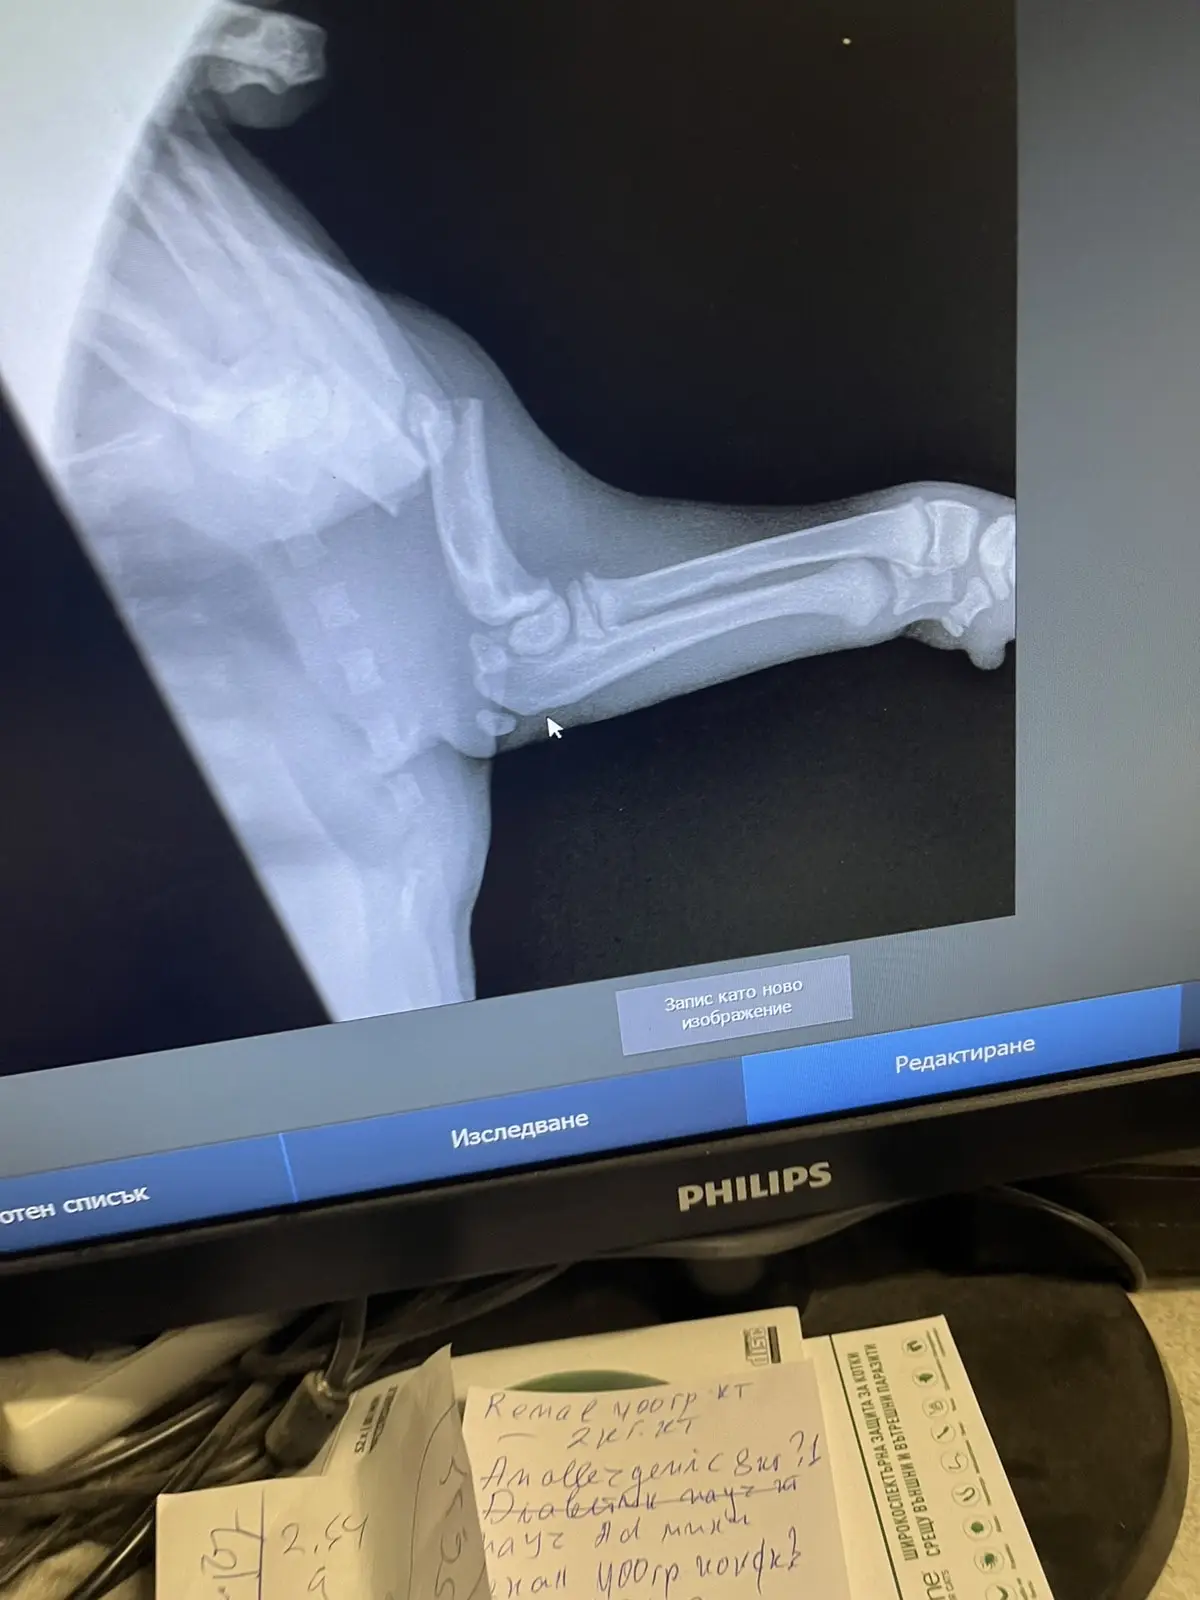

Вчера открихме Скай в шоково състояние. Не знаем със сигурност какво се е случило – дали е блъсната от кола, или по-лошото – дали е станала жертва на човешка жестокост и е била ритната. Резултатът обаче е съкрушителен: тежко счупена предна лапа в областта на рамото и кръвоизлив в главата.

• Спешни изследвания, рентгени и скъпоструващи медикаменти за кръвоспиране и неврологична подкрепа.